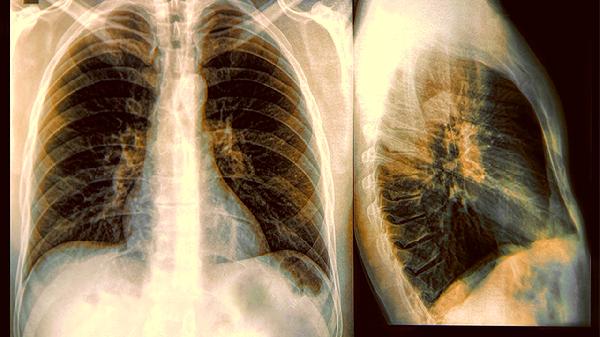

想象一下,你正惬意地躺在沙发上,享受着加湿器喷出的细腻水雾,却不知道这个看似温柔的"小帮手"可能正在悄悄制造健康隐患。最.近有研究发现,不当使用加湿器可能成为呼吸道疾病的隐形推手,甚至有人因此患上"加湿器肺炎"。这不是危言耸听,而是真实存在的健康风险。

为了让空气更"健康",有些人会在加湿器中添加精油或消毒剂。这些化学物质被雾化后,会刺激呼吸道黏膜,破坏肺部防御机制。特别是对儿童和过敏体质人群,可能诱发哮喘或过敏性肺炎。

不少人喜欢24小时开着加湿器,认为这样能保持空气湿度恒定。但过度加湿会导致室内湿度过高,为霉菌和尘螨繁殖创造了理想环境。这些过敏原会随着呼吸进入人体,增加呼吸道感染风险。